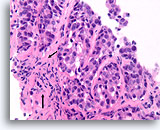

Ductaal carcinoom, Borst FNA, Celblok.

Let op de onregelmatige contour van de solide, smalle strengen met infiltratieve cellen (pijlen).

60X

Ductaal carcinoom, Borst FNA, Celblok.

Let op de onregelmatige contour van de solide, smalle strengen met infiltratieve cellen (pijlen).

60X